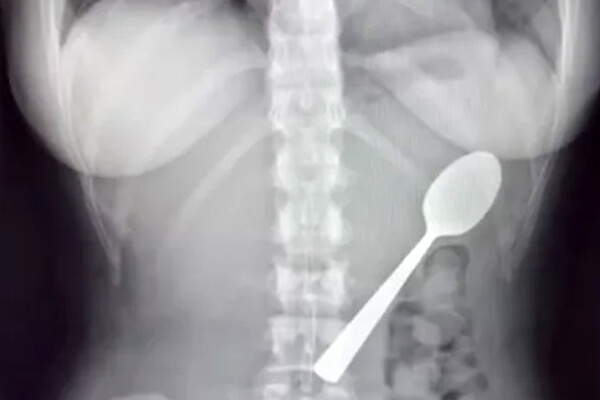

Девушка испугалась собаки и случайно проглотила 17-сантиметровую ложку

В Бельгии спасли девушку, которая из-за испуга проглотила длинную ложку

В Бельгии девушка случайно проглотила к 17-сантиметровую ложку из-за внезапного испуга, пишет What's The Jam.

Необычный случай произошел с 28-летней Рейми Амелинкс из Румста. Ее энергичная собака породы венгерская выжла по кличке Марли внезапно запрыгнула на колени, заставив Рейми резко дернуться. Девушка зажала ложку зубами, так как печатала двумя руками сообщение, поэтому предмет застрял в горле.

Врачи предупредили, что такая большая ложка не выйдет естественным путем, и назначили гастроскопию через два дня. Под местной анестезией ее повернули в желудке и удалили.